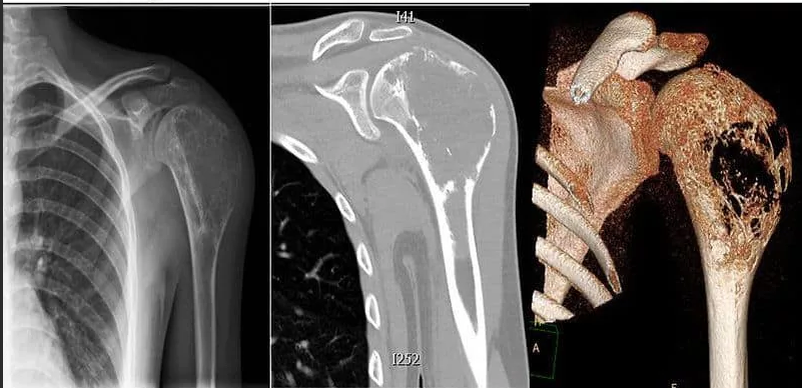

•  Всем пациентам с подозрением на остеосаркому или саркому Юинга рекомендовано проведение рентгенографии области первичного поражения в двух проекциях с масштабной разметкой для первичной диагностики опухолевого образования, а также оценки наличия мягкотканного компонента и периостальной реакции [5,9,11].

Комментарий: Характерные симптомы остеосаркомы — очаг деструкции, игольчатый периостит, «козырек» Кодмана [11], характерный симптом саркомы Юинга - луковичный периостит [6].

•  Всем пациентам с подозрением на остеосаркому или саркому Юинга рекомендовано проведение компьютерной томографии (КТ) пораженной области с контрастным усилением [5,9,11].

Комментарий: КТ обязательно должна захватывать всю анатомическую область поражения целиком. В случае КТ таза должен быть снят весь таз, а не его пораженная половина, в случае КТ конечностей, обязательно должны быть захвачены два смежных сустава (для бедренной кости коленный и тазобедренный сустав, для большеберцовой кости - голеностопный и коленный и т.д.). При наличии противопоказаний к введению контрастного вещества КТ может быть выполнена без контраста.